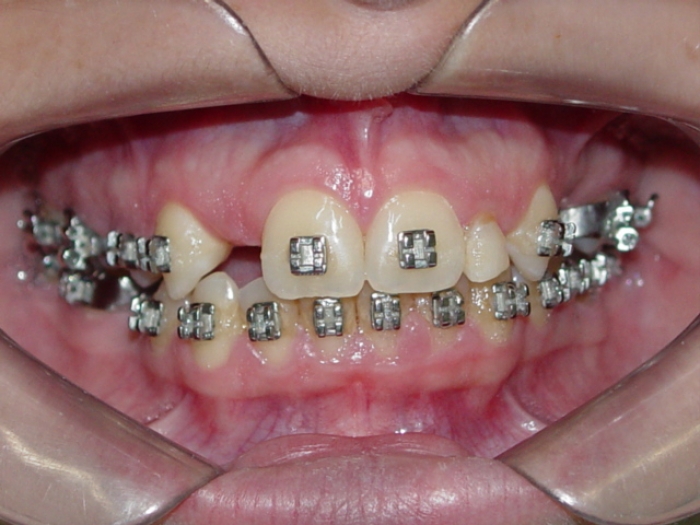

Imagem inicial